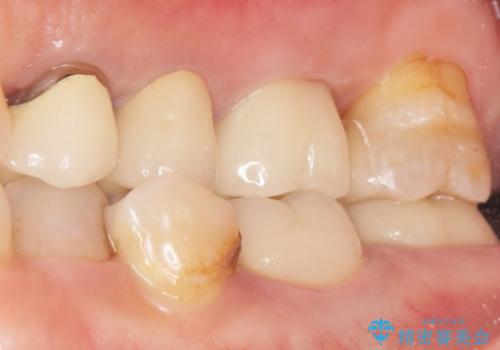

そのためラバーダム(ゴムのシート)をつけることで、詰め物が口腔内に飛んだり破片が飛び散ったりしないよう配慮し治療を行いました。

患者様のご希望により、左上6クラウン、左上7インレーによるセラミック治療を行いました。

再根管治療はご希望されなかったため行っておりません。